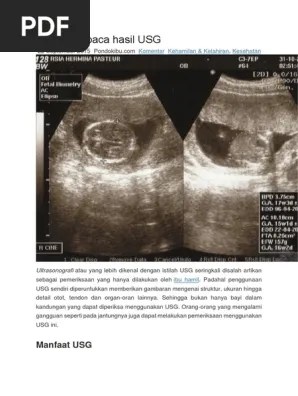

Cara Membaca Hasil USG Berdasarkan Singkatan | Kehamilan sehat, Kehamilan, Kesehatan bayi